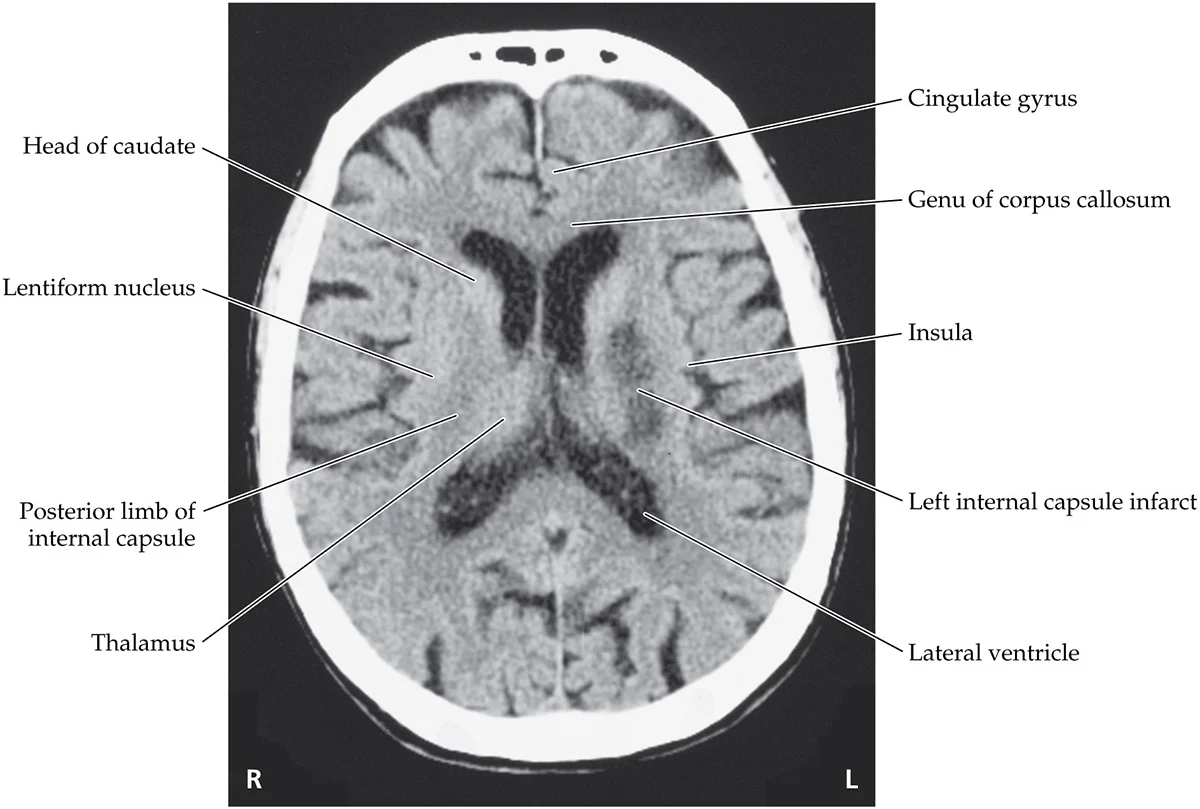

An 84-year-old woman with a history of hypertension and diabetes had two episodes of slurred speech and right-sided weakness on two consecutive days, and on the third day she developed persistent dysarthria and right hemiplegia. Exam was normal except for right facial weakness sparing the forehead, dysarthria, decreased right-sided tone, 0/5 power in the right arm and leg, and right upgoing plantar response

Internal capsule infacts, occlusion of lenticulostriate arteries. MCA